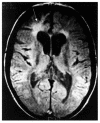

Human African trypanosomiasis (HAT), also known as sleeping sickness, is a major cause of mortality and morbidity in sub-Saharan Africa. Current therapy with melarsoprol for CNS HAT has unacceptable side-effects with an overall mortality of 5%. This review discusses the issues of diagnosis and staging of CNS disease, its neuropathogenesis, and the possibility of new therapies for treating late-stage disease.